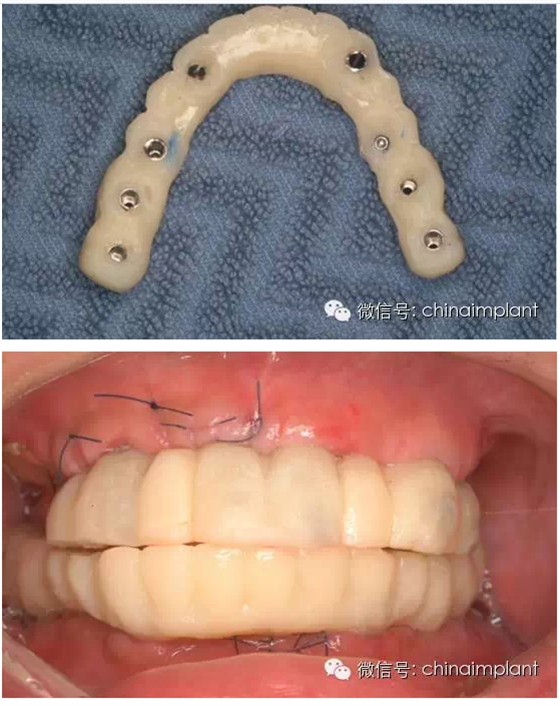

此案例為術(shù)后兩周戴臨時(shí)牙。過去因?yàn)閾?dān)心感染的問題,一個(gè)月以內(nèi)帶臨時(shí)牙也叫做即刻負(fù)重或者早期負(fù)重。(現(xiàn)在當(dāng)天戴臨時(shí)牙(即刻復(fù)重)的情況也非常常見).

之前針對全口無牙進(jìn)行種植修復(fù)的案例中,因?yàn)轭M骨的原因,后期使用橋冠修復(fù)時(shí),一般是3部分(兩側(cè),磨牙,前牙),最近的案例中修復(fù)是一般都是做一體式的橋冠,現(xiàn)在從臨床的修復(fù)案例來看,沒有什么問題。